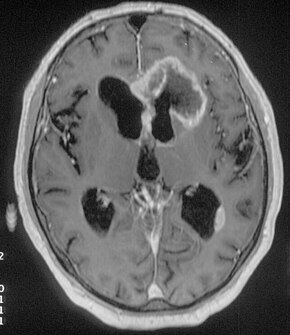

An MRI image of a brain with an invasive, multilocular tumor in the left frontal lobe of the brain.